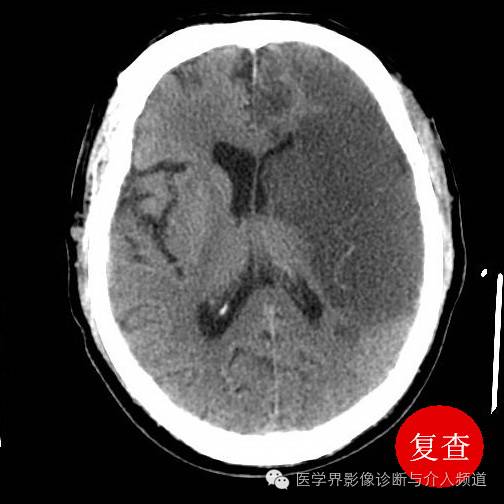

术前头颅ct示左侧大脑中动脉大面积脑梗塞,患者浅昏迷,右侧肢体偏瘫

术前头颅ct可见右侧大脑中动脉血栓 aspects评分 10分